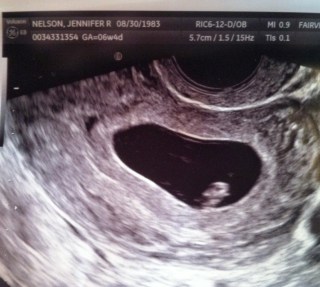

Today we had our first ultrasound. And there is a heartbeat. Thank you, Universe and Divinity and All That Is Good, there is a heartbeat. Strong and regular. Perfect. I cried a bunch, and then we went out for Mexican food because I was starving.

Second ultrasound today. Matt’s in Brazil for work, so Deb O came with me (thanks, MIL!). The grainy footage showed us, amazingly, our baby’s tiny limbs and strong heartbeat. And we saw it move. It was moving. Ten weeks old, the size of a lima bean, and moving around. I am in love.